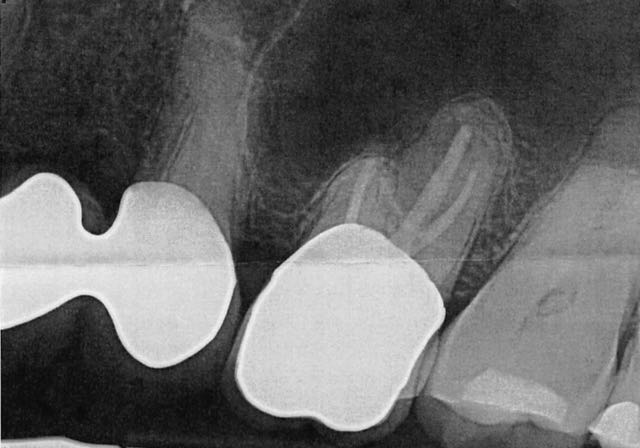

Exposure of Impacted Canine and Extraction of Adjacent Impacted Lateral Incisor

In this video, Dr. H. Ryan Kazemi presents a patient with delayed eruption of upper canine and lateral incisor and demonstrates the exposure and extraction technique.